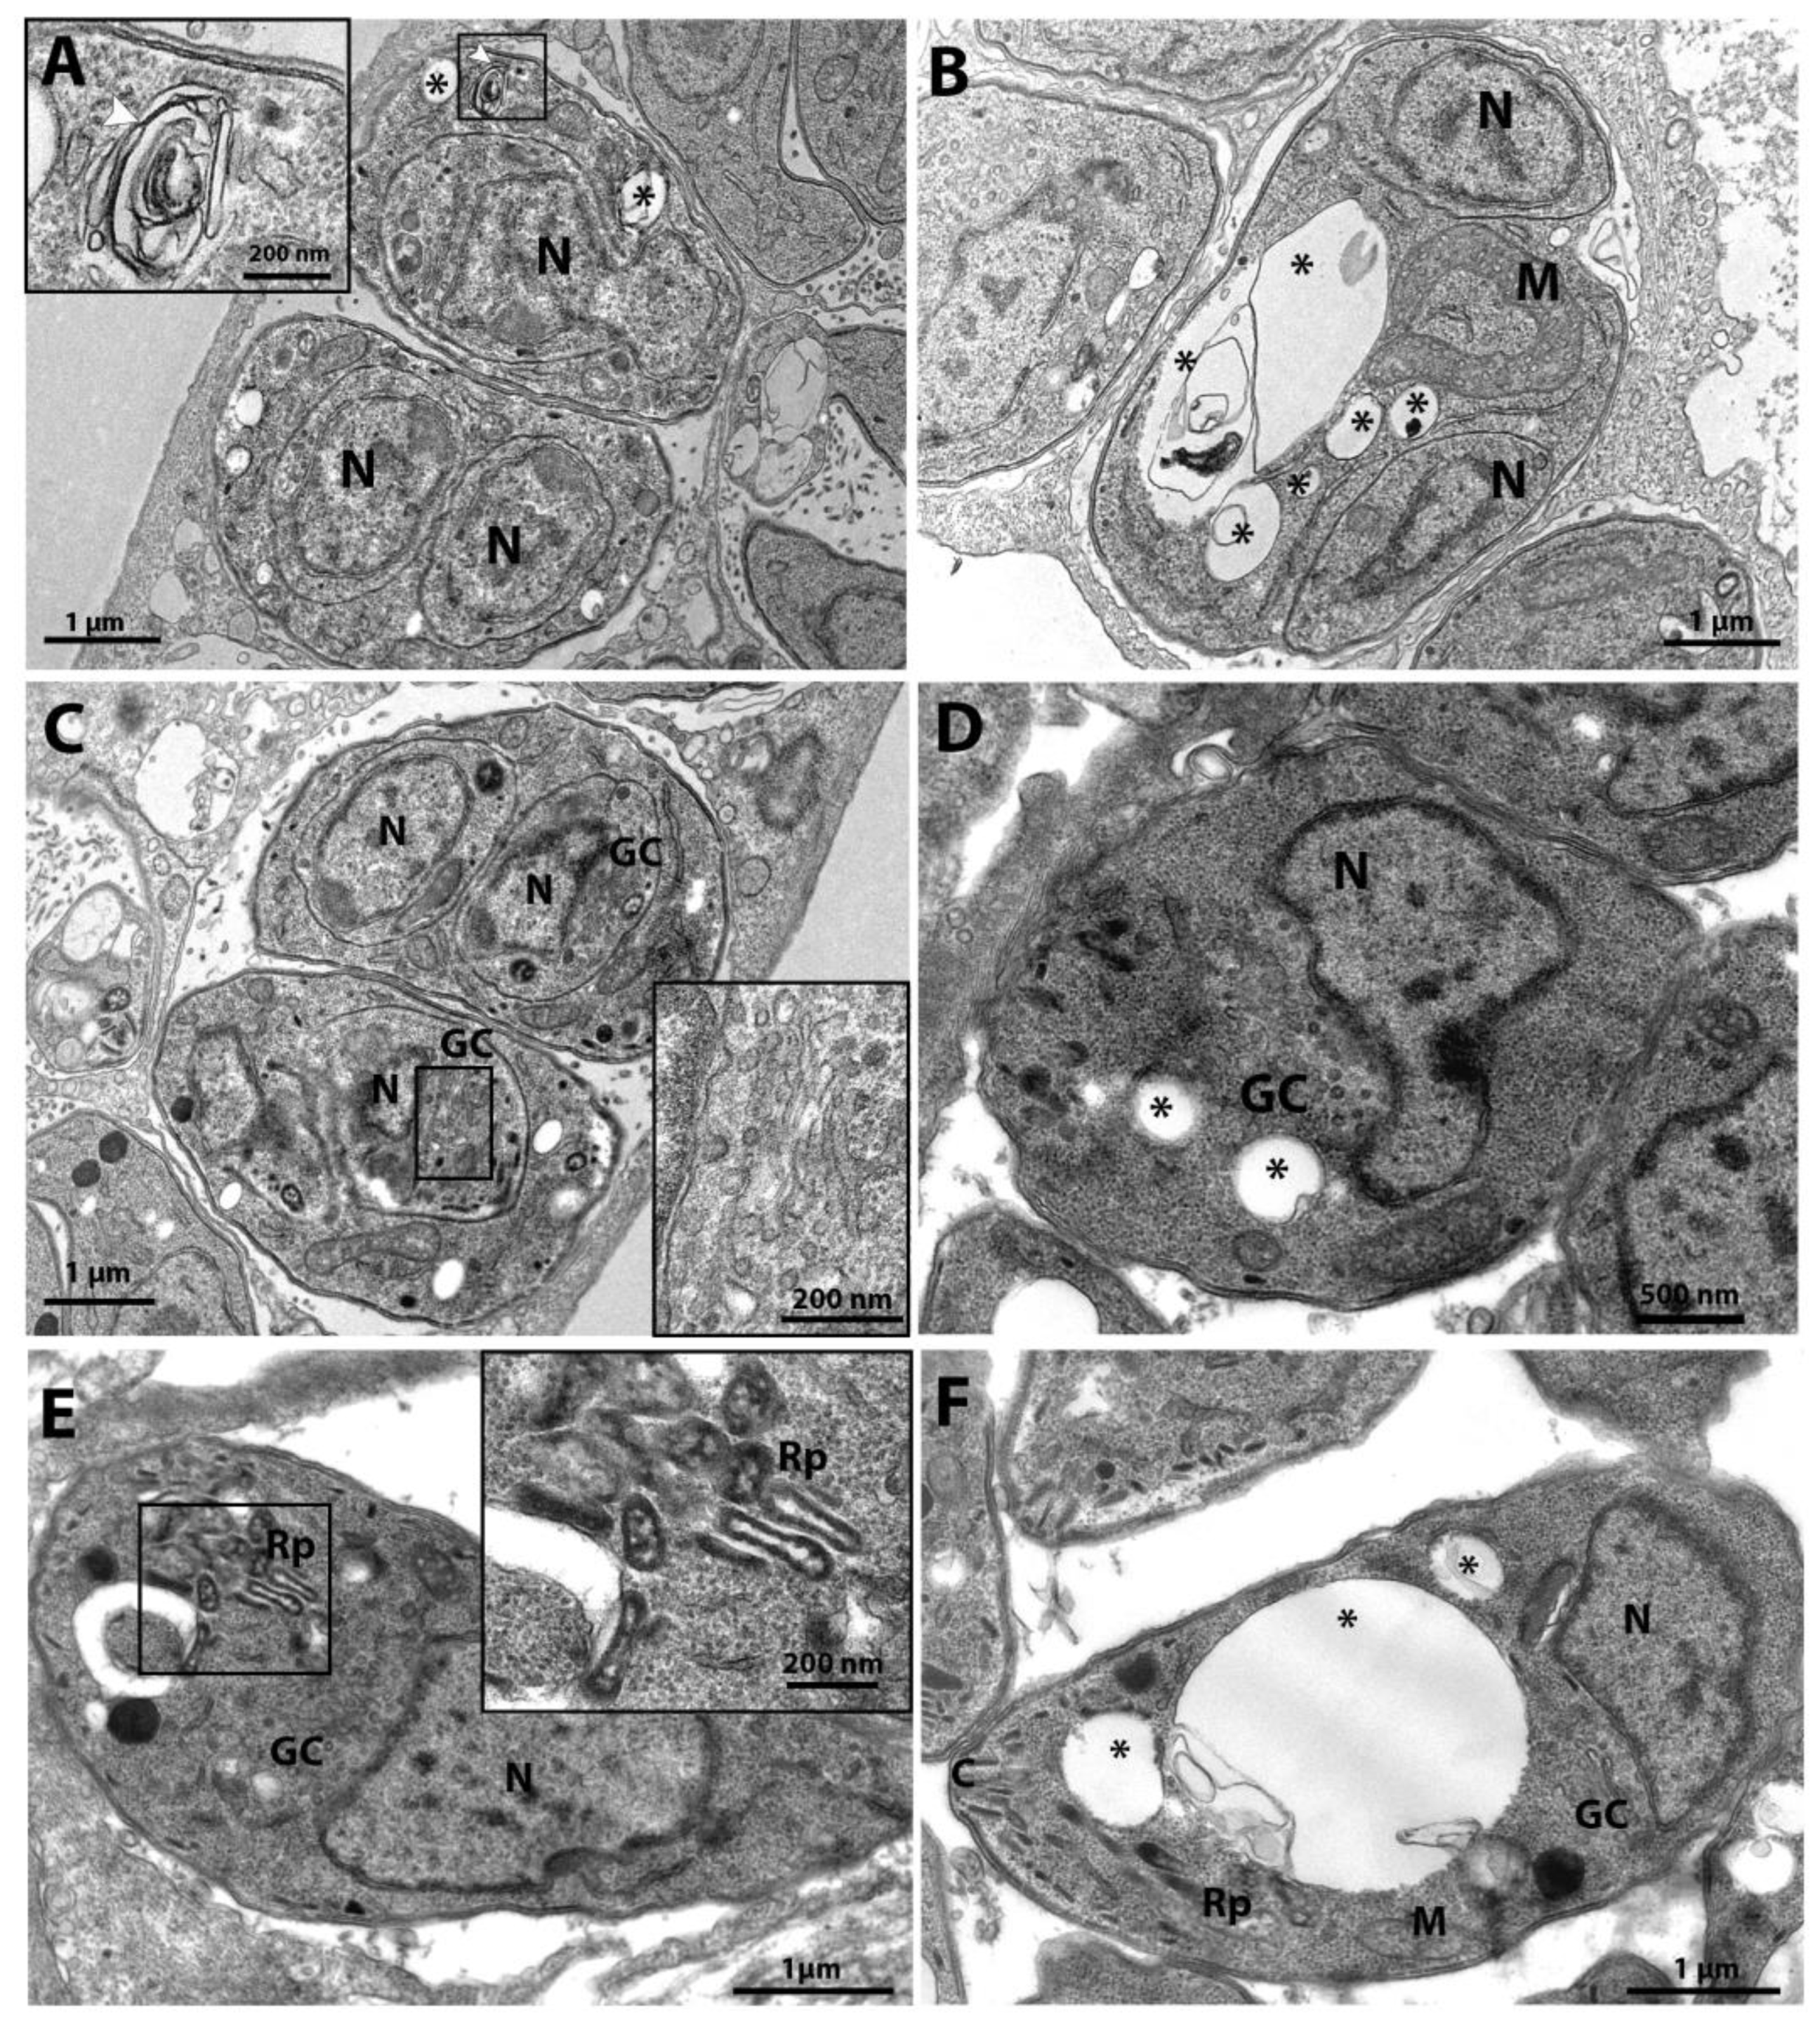

3.3. Analysis of the Effect on Ultrastructure Induced by Drugs and Compounds of Covid-Box by Transmission Electron Microscopy (TEM)